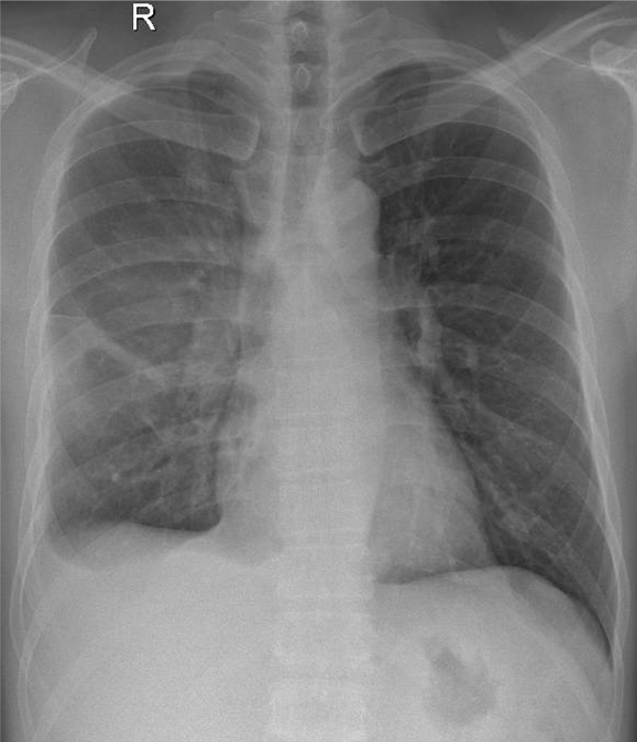

1-Tổn thương mờ đồng nhất vùng quanh rốn 1/3 giữa phổi (P) => Viêm phổi 2-Tràn dịch màng phổi (P) lượng ít